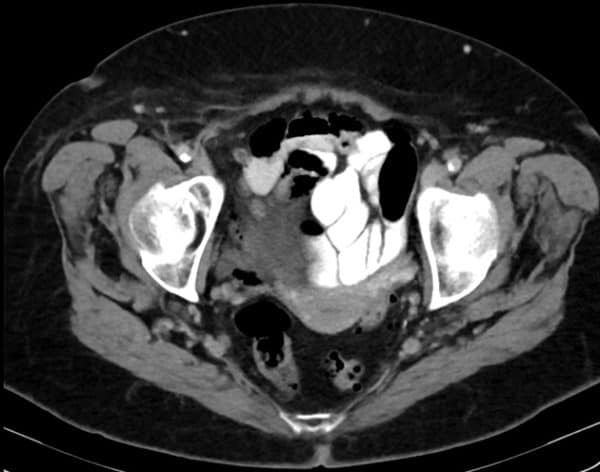

Thoát vị De Garengeot

» Thông tin: Nữ giới – 85 tuổi.

» Lâm sàng: Đau háng phải.